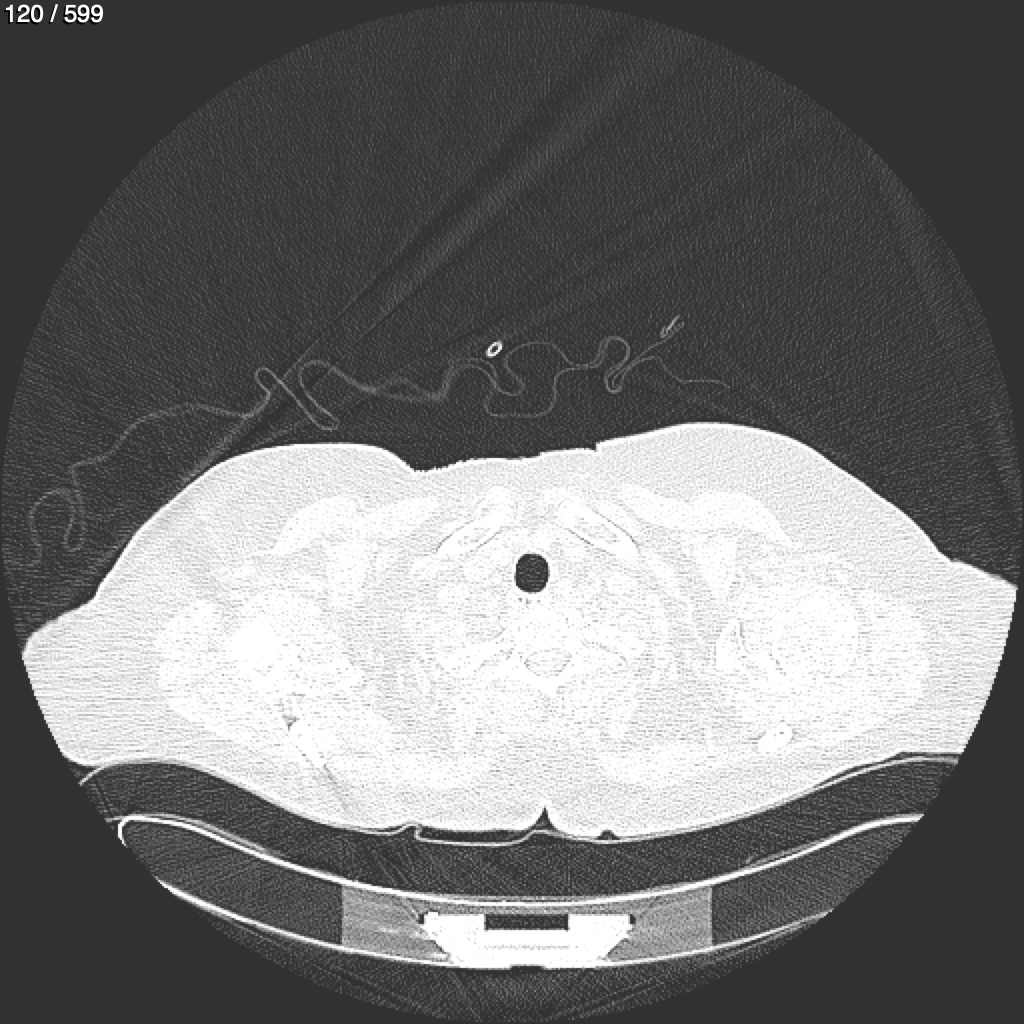

Home G​l​o​r​i​a​ ​G​l​a​d​y​s​ ​B​e​a​s​l​e​y​ ​-​ ​T​ó​r​a​x​ ​T​o​r​a​x​_​S​i​m​p​l​e​ ​(​A​d​u​l​t​o​)